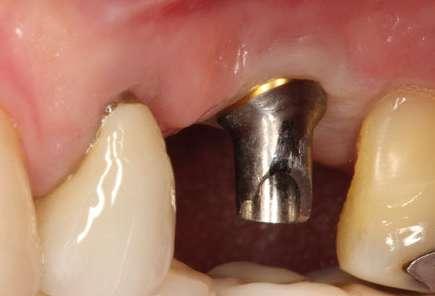

Figuras 3-6. Imágenes de un caso de prótesis atornillada en molar unitario inferior. Vemos el estado de los tejidos blandos gingivales tras la segunda fase y colocación del transepitelial unitario y la radiografía. En las imágenes inferiores (5 y 6) observamos el caso a los 4 años y 10 años de seguimiento, con estabilidad completa de los tejidos óseos peri-implantarios.

Figuras 7-10. En las dos imágenes superiores (7 y 8) observamos la realización de la prótesis cementada mediante un bioplilar fresado a la altura gingival con la radiografía antes del cementado de la corona. En las imágenes inferiores (9 y 10) vemos la prótesis a los 7 años de seguimiento y a los 9 años transformada en una prótesis atornillada al perderse la pieza anterior al implante y realizarse un puente con el nuevo implante. En este caso, el nivel óseo permanece estable con el paso del tiempo.